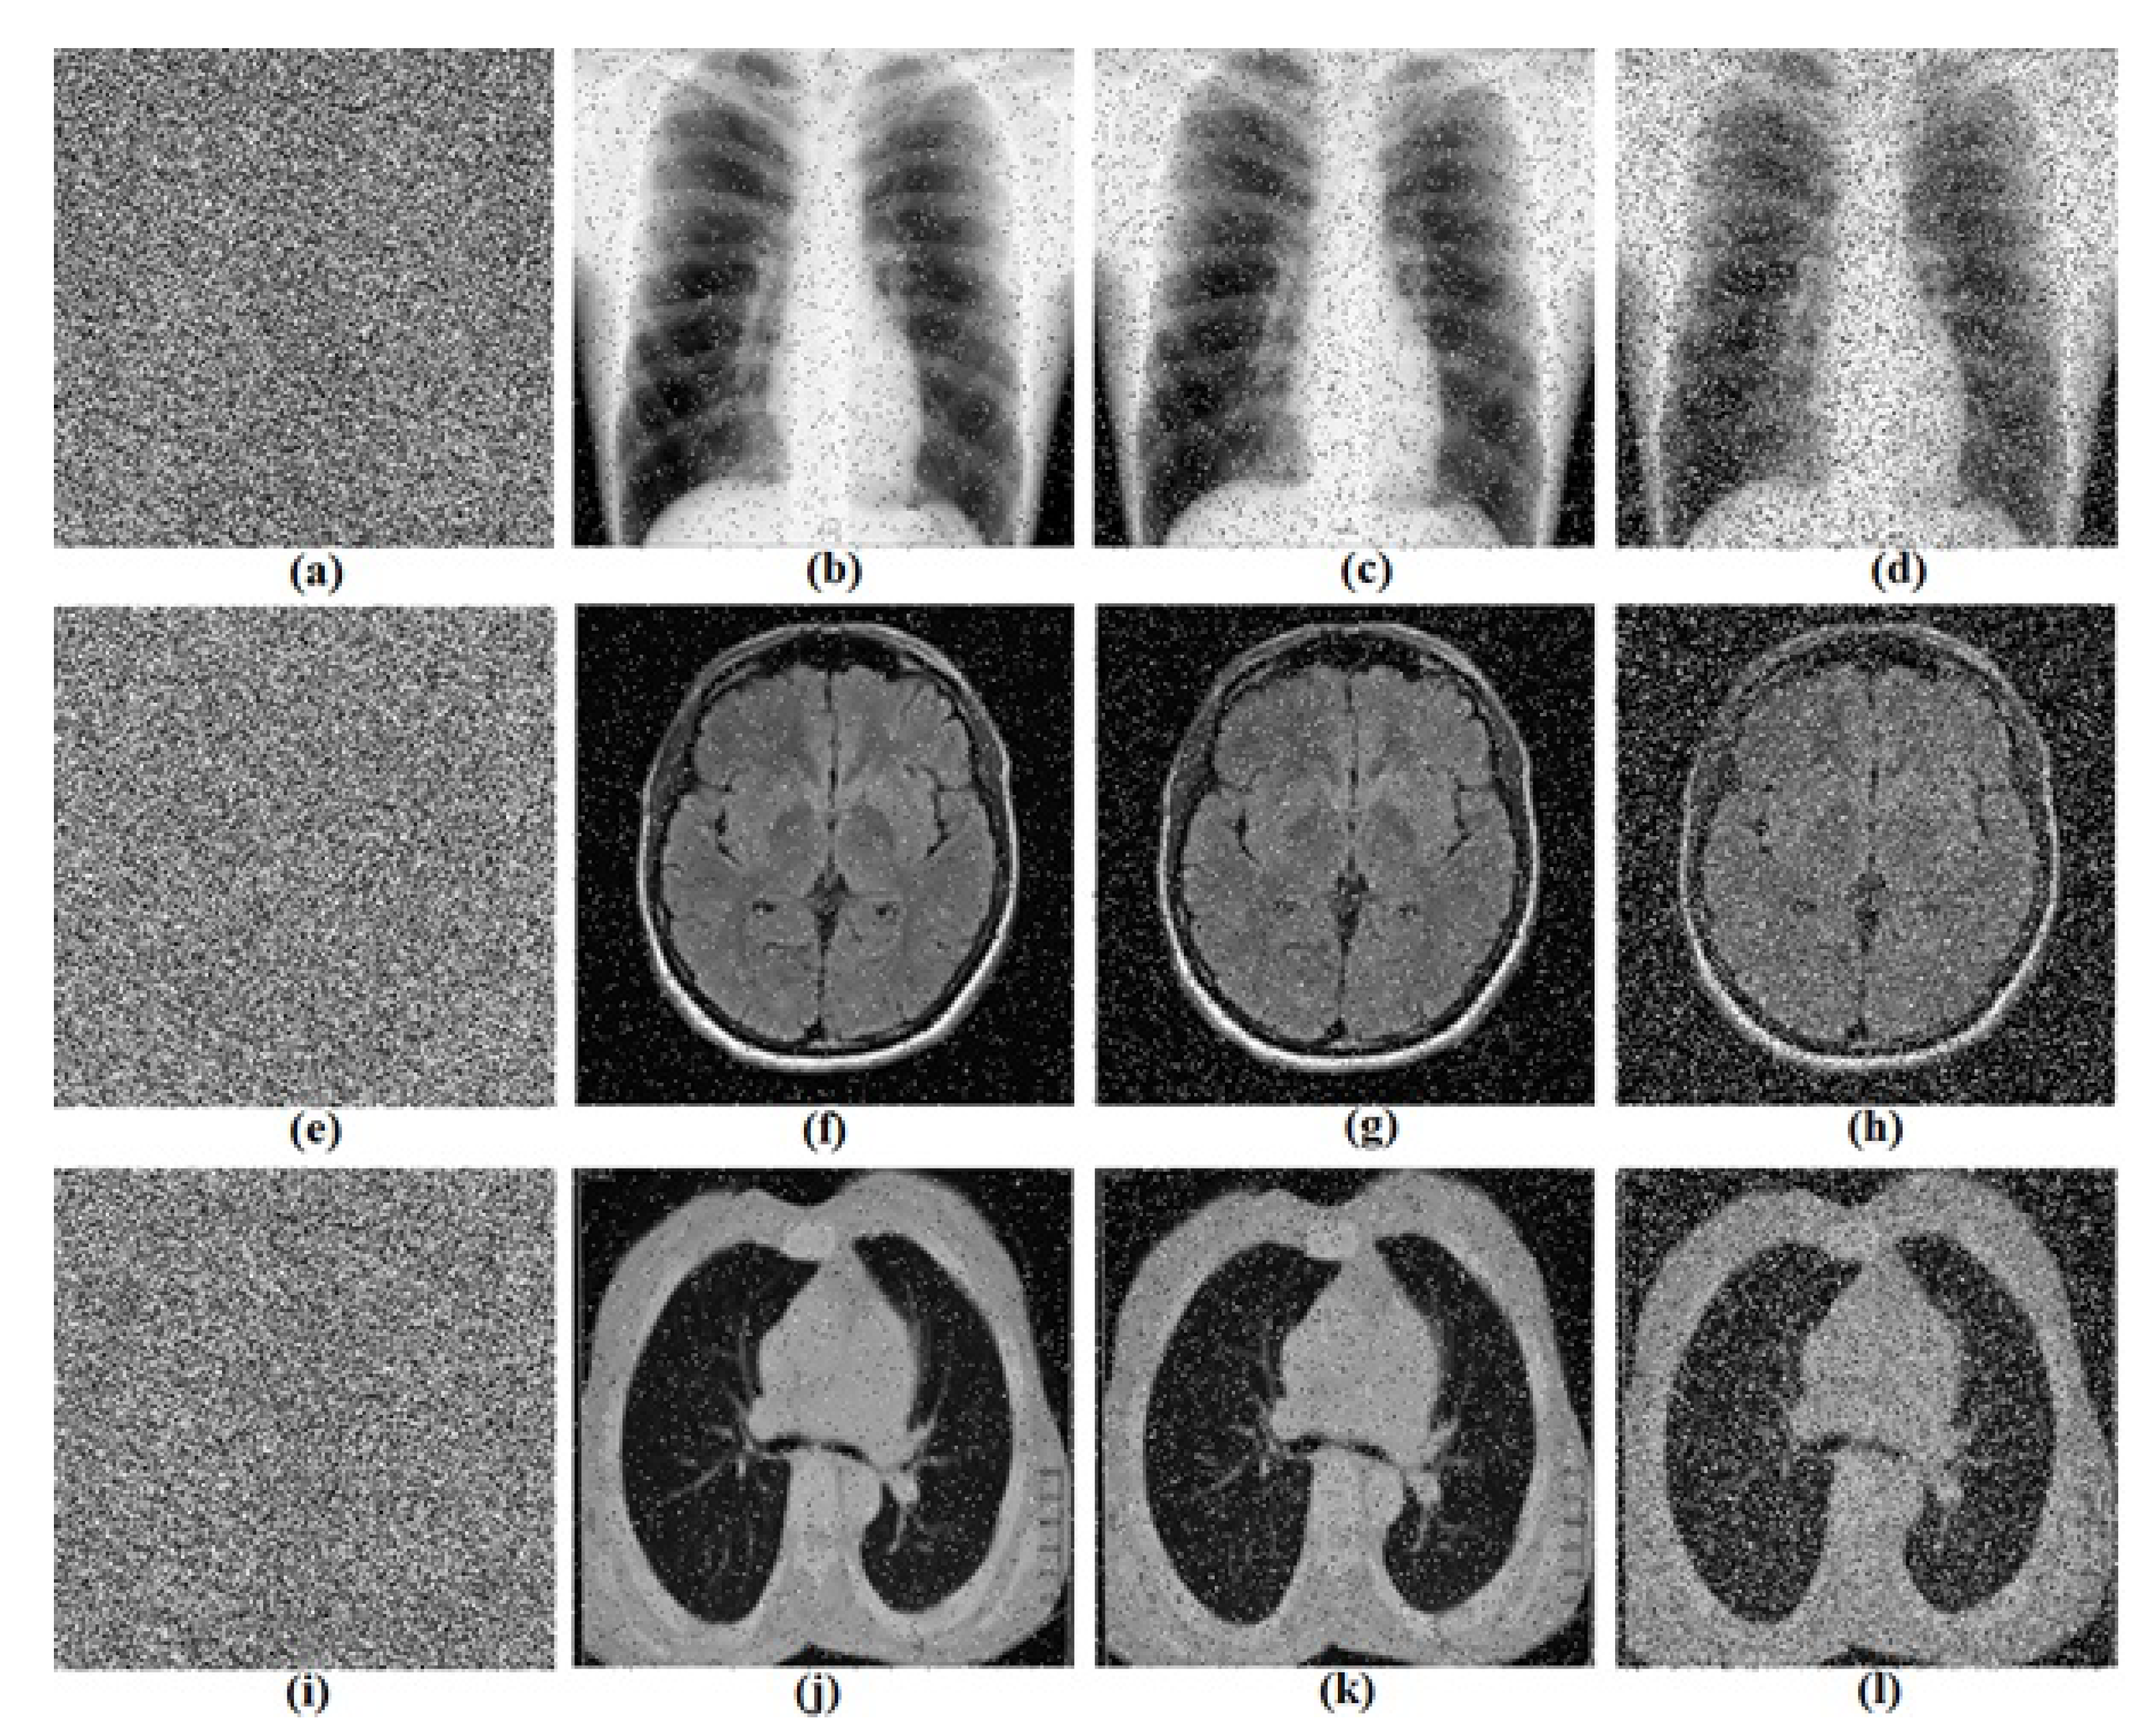

5.2. Computational Results

5.3.4. Noise Attacks